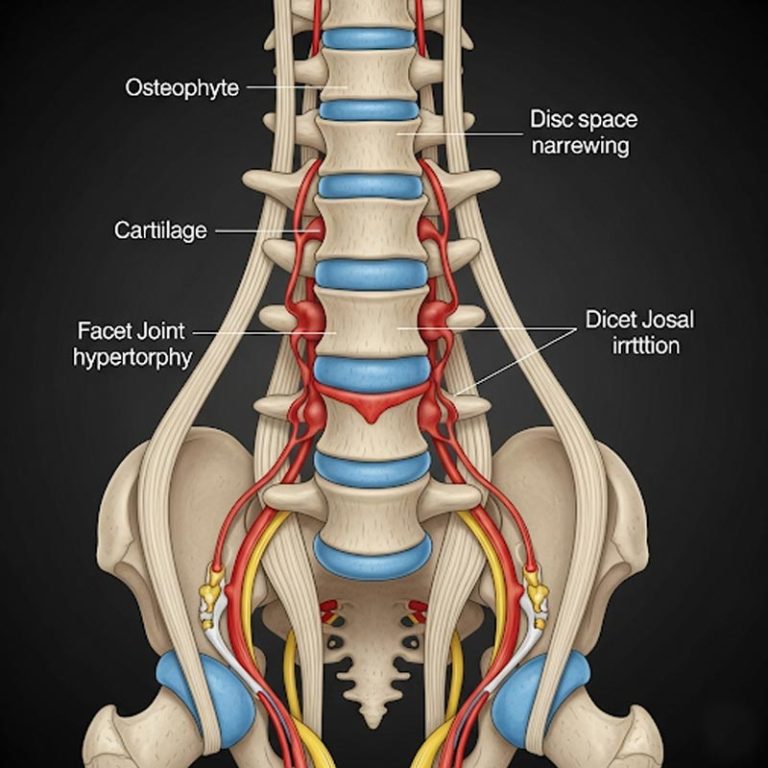

ChatGPT said: Spondylosis is a general term for age-related wear and tear of the spine, particularly...

Degenerative Disc Disease (DDD) is a condition where the spinal discs, which act as cushions between...

Spinal Canal Stenosis is a condition where the space within the spinal canal narrows, putting pressure...

Spondylolisthesis is a spinal condition where one vertebra slips forward over the one below it, often...